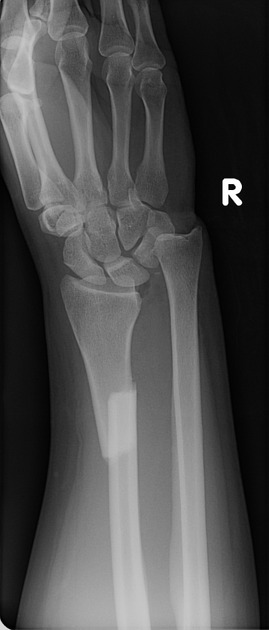

colles’ fracture

26

New cards

smith’s fracture